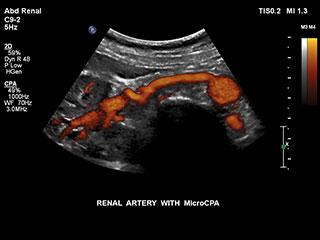

Ultrasound MicroCPA Small Vessel Visualization

MicroCPA

これまで、血流が少ない血管構造の血流情報は容易に収集できませんでした。しかし、EPIQの新しいMicroCPA機能を使用することで、低流速の微小循環を素早くかつ簡潔に描出できるようになり、臓器への灌流や小血管床の評価における診断確度が向上しました。